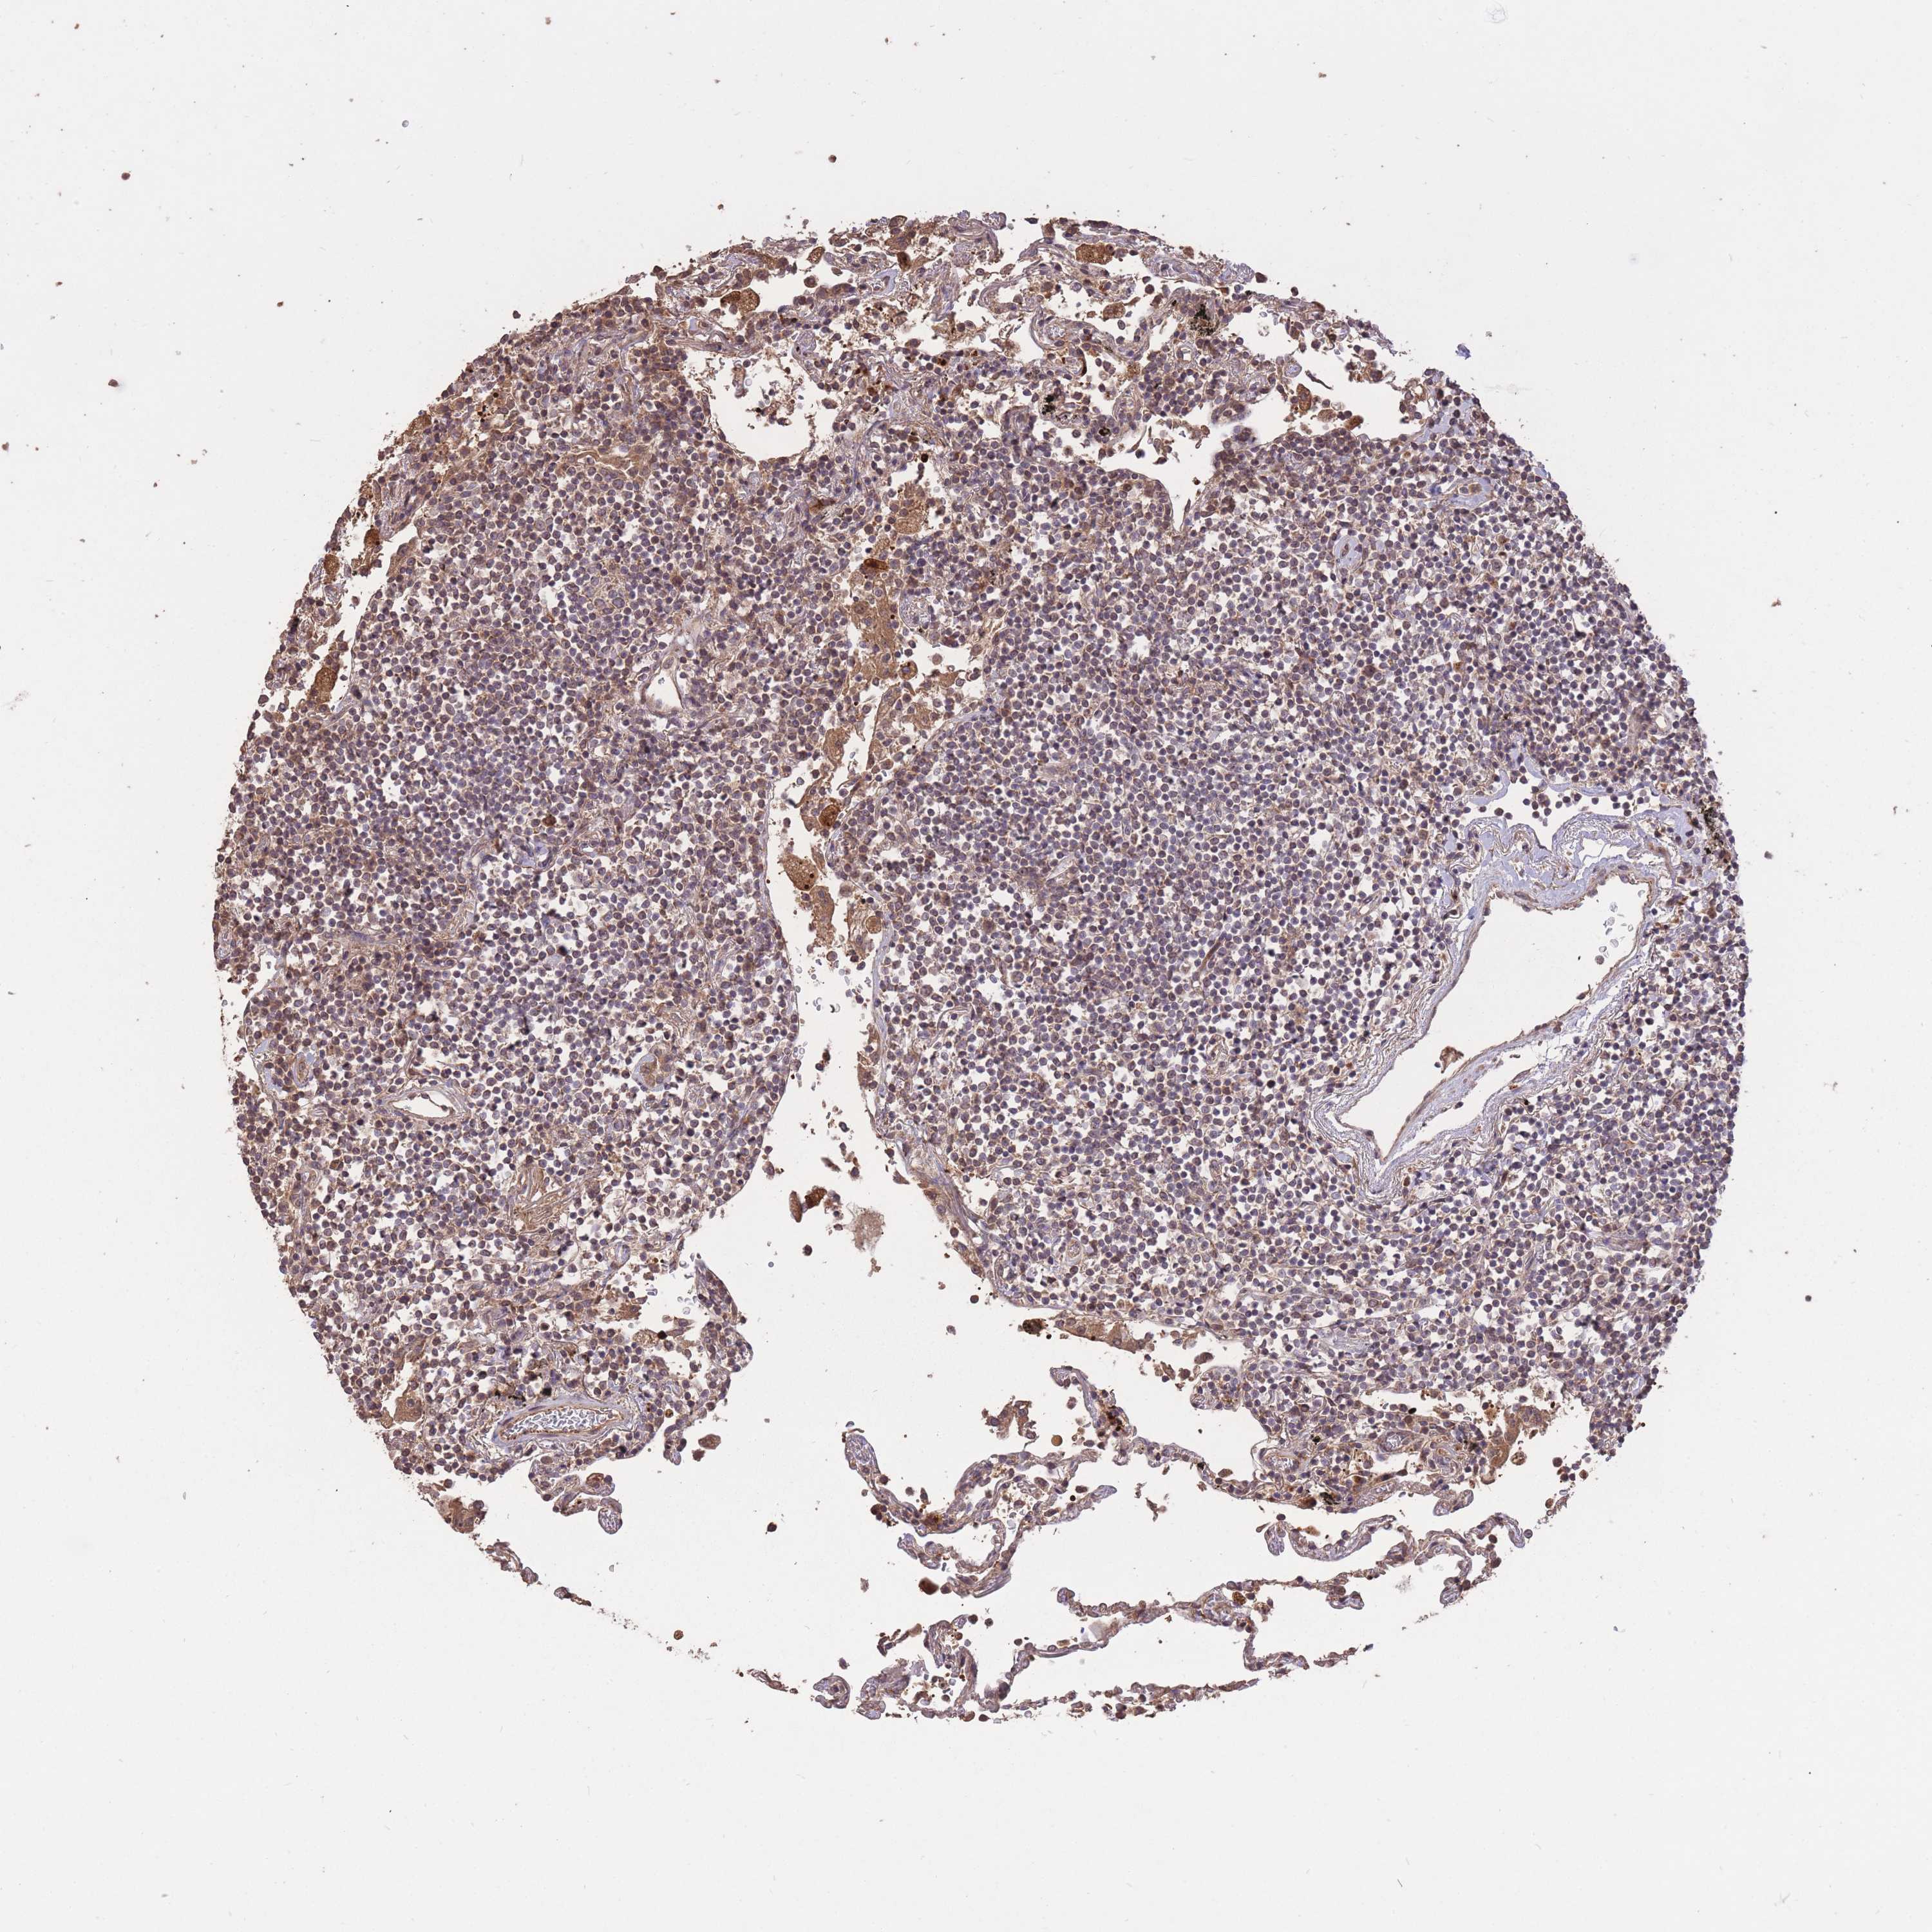

CANCER LYMPHOMA Show tissue menu

LYMPHOMA - Protein expressioni

A mouse-over function shows sample information and annotation data. Click on an image to view it in a full screen mode. Samples can be filtered based on level of antibody staining by selecting one or several of the following categories: high, medium, low and not detected. The assay and annotation is described here.

Each image is clickable and will lead to virtual microscopy that enables deeper exploration of all samples and also displays staining intensity scores, fraction scores and subcellular localization as well as patient and tissue information for each sample.

Antibody HPA045396

Antibody HPA070524

Antibody CAB025331

Staining

High

Medium

Low

Not detected

Intensity

Strong

Moderate

Weak

Negative

Quantity

>75%

75%-25%

<25%

None

Location

Nuclear

Cytoplasmic/membranous

Cytoplasmic/membranous,nuclear

Hodgkin's disease, NOS

Malignant lymphoma, non-Hodgkin's type, High grade

Malignant lymphoma, non-Hodgkin's type, Low grade